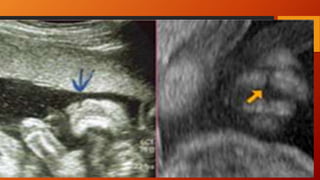

LABIO LEPORINO YFISURA PALATINA • El labio leporino típico aparece como un defecto lineal que se extiende desde el borde superior del labio hasta la fosa nasal Puede estar asociado a fisura palatina, que puede abarcar el paladar blando, el duro, el suelo de la cavidad nasal o incluso el de la órbita. En el 75% de los casos, el defecto es unilateral, y afecta más al lado derecho. • La frecuencia es de 1/800, y en un 50% la alteración aparece de forma asilada (aislada (únicamente labio leporino o fisura palatina) o conjunta. Habitualmente es un hallazgo aislado, pero en un 20% de los casos puede ir asociado a alteraciones genéticas. • Las trisomías 13 y 18 son las más frecuentes. También se ha visto asociado a teratógenos como fármacos antiepilépticos. • El diagnóstico ecográfico se realiza en un corte coronal de la cara, donde en el labio superior se objetiva una zona anecoica, lineal, desde la fosa nasal hasta el labio superior

Para el diagnósticodel paladar hendido se necesitan cortes transversos. Para el diagnóstico del paladar hendido se necesitan cortes transversos.

Diagnostico Demostrar el surcoo la solución de continuidad a nivel del labio y/o del paladar.  Corte frontocoronal tangencial: imprescindible para el diagnóstico y para establecer bilateralidad.  Corte transversal a nivel del maxilar nos permitirá comprobar la continuidad de los alveolos dentarios y por tanto, descartar o confirmar la presencia de una fisura palatina